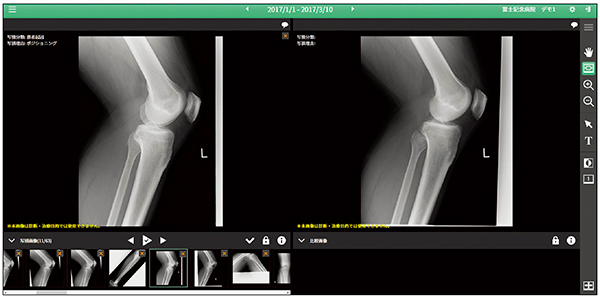

写損カンファレンス機能(図3)では,簡単に写損要因の検証が行えます。撮影室やポータブルに配置された画像処理ユニットConsole Advanceより,写損キーが押された検査画像のすべてを自動で収集します。送られた画像は撮り直し画像と比較できるよう保管されます。写損カンファレンス機能は,写損率,写損枚数で必要な絞り込みを行った状態で起動可能です。また,Windows標準リモートデスクトップ機能が使用できますので,離れた場所のモニタやプロジェクタで投影し表示可能です。

図3 写損カンファレンス画面